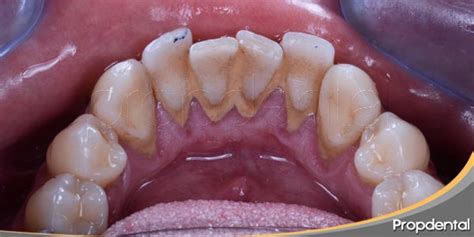

El sarro dental, también llamado cálculo dental, es una placa bacteriana que se ha endurecido debido a los minerales presentes en la saliva. Todo comienza con la placa dental, una película transparente y pegajosa que se forma constantemente en nuestros dientes. Si no se elimina correctamente (con un buen cepillado y el uso de hilo dental), esta placa se mineraliza y se convierte en sarro, especialmente en zonas como detrás de los dientes inferiores.

El sarro, o cálculo dental, es placa bacteriana que se ha endurecido por los minerales de la saliva. La mala higiene bucodental es la principal causa de su aparición.